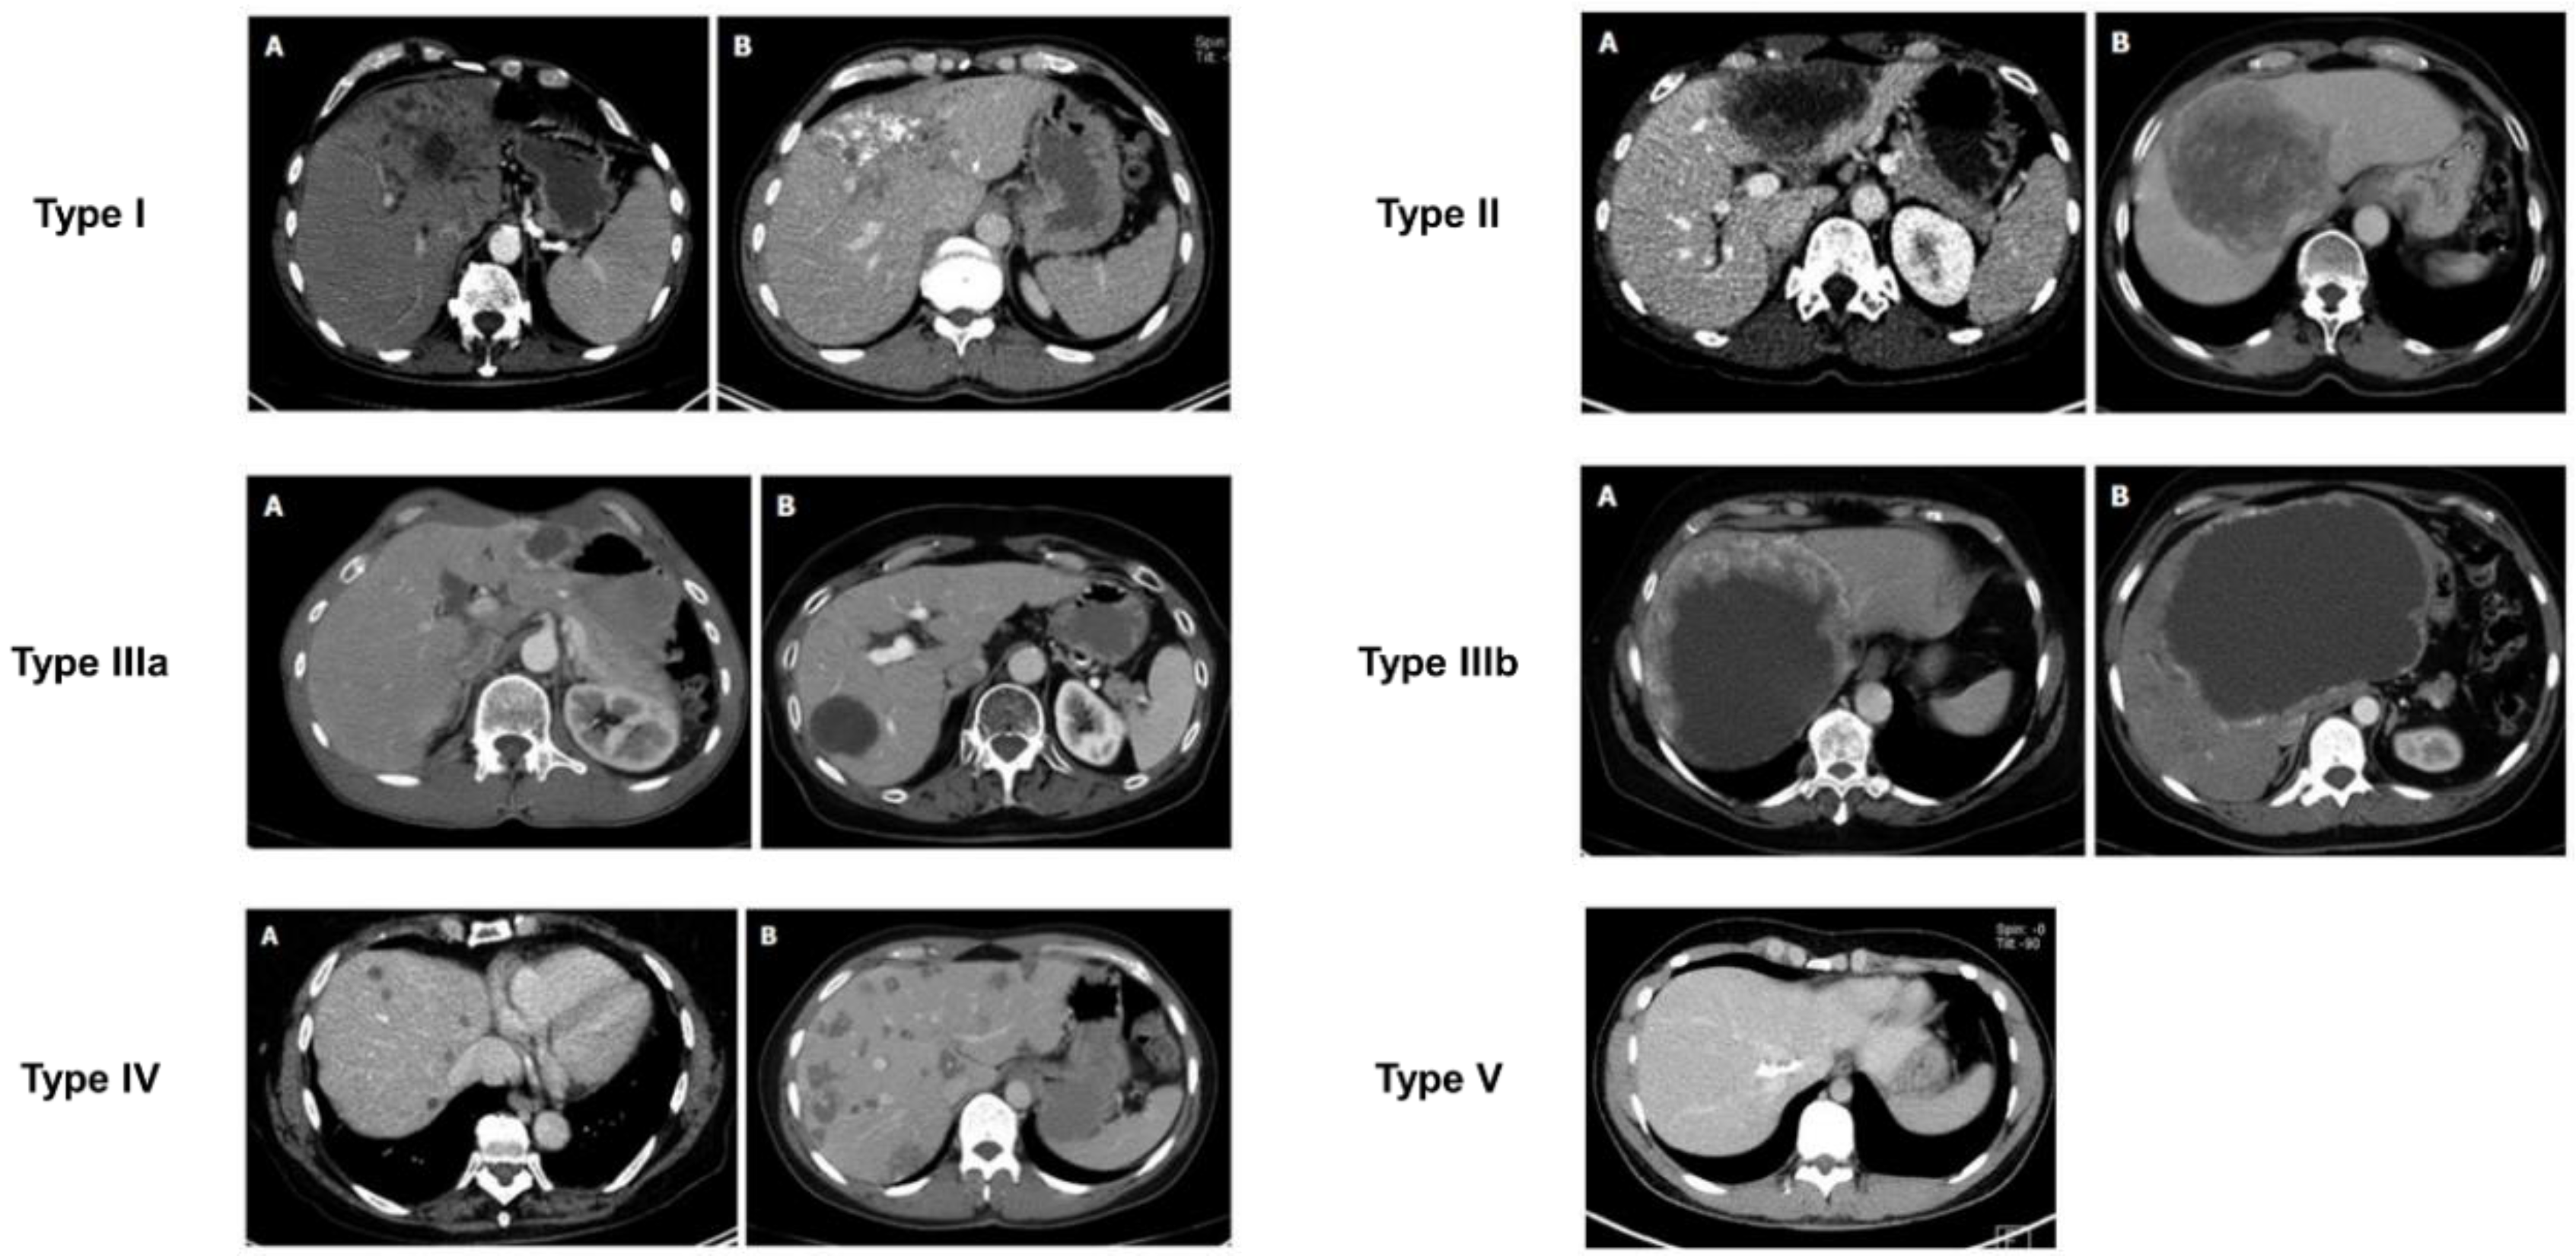

Besides the US, computed tomography (CT) is presently the preferred diagnostic imaging among the available methods, as it is capable of detecting the highest number of lesions and clearly distinguishing characteristic calcifications [111,112]. Abdominal CT is more suitable for identifying calcifications and preoperative assessment. CT scan primarily relies on the determination of lesion size, rather than on the accurate assessment of AE proliferation and infiltration activity. In 2016, Graeter et al. [113] proposed five classifications for CT imaging of hepatic alveolar echinococcosis (Figure 5). Type I: diffuse infiltrating, Type II: primarily circumscribed tumor-like, Type III: primarily cystoid, Type IV: small-cystoid/metastatic, Type V: mainly calcified. After conducting a retrospective analysis of 228 patients with hepatic alveolar echinococcosis, they revealed that the most frequently encountered CT morphological pattern was the diffuse infiltration pattern (Type I), followed by the primarily circumscribed tumor-like appearances (Type II). The mainly calcified appearance (Type V) was observed less frequently. The E. multilocularis Ulm classification for computed tomography (EMUC-CT) offers the basis for the systematic description of the CT morphology of AE lesions of the liver [114]. A study has shown that there is a close correlation between the patterns of AE according to the EMUC-CT classification and the different histological patterns of AE infections [79]. The CT types mark consecutive stages of infection, which progress over time. The classification of calcifications in AE observed on CT is shown in Figure 6.

Figure 6. Patterns of calcification [124]. The calcification of AE in CT images is classified into five stages: no calcifications; feathery calcifications; focal calcifications; diffuse calcifications; calcifications primarily at the edge and central calcification.